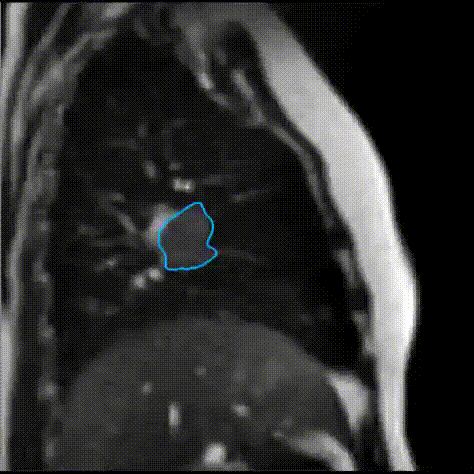

Our group is currently working on developing next-generation cardiovascular MR techniques and pushing the speed limit of MR aiming for MR-guided treatment.

High-resolution single-sequence multi-parametric cardiac MRI integrated with AI to optimize data acquisition, motion correction, image reconstruction, and cardiac disease diagnosis.